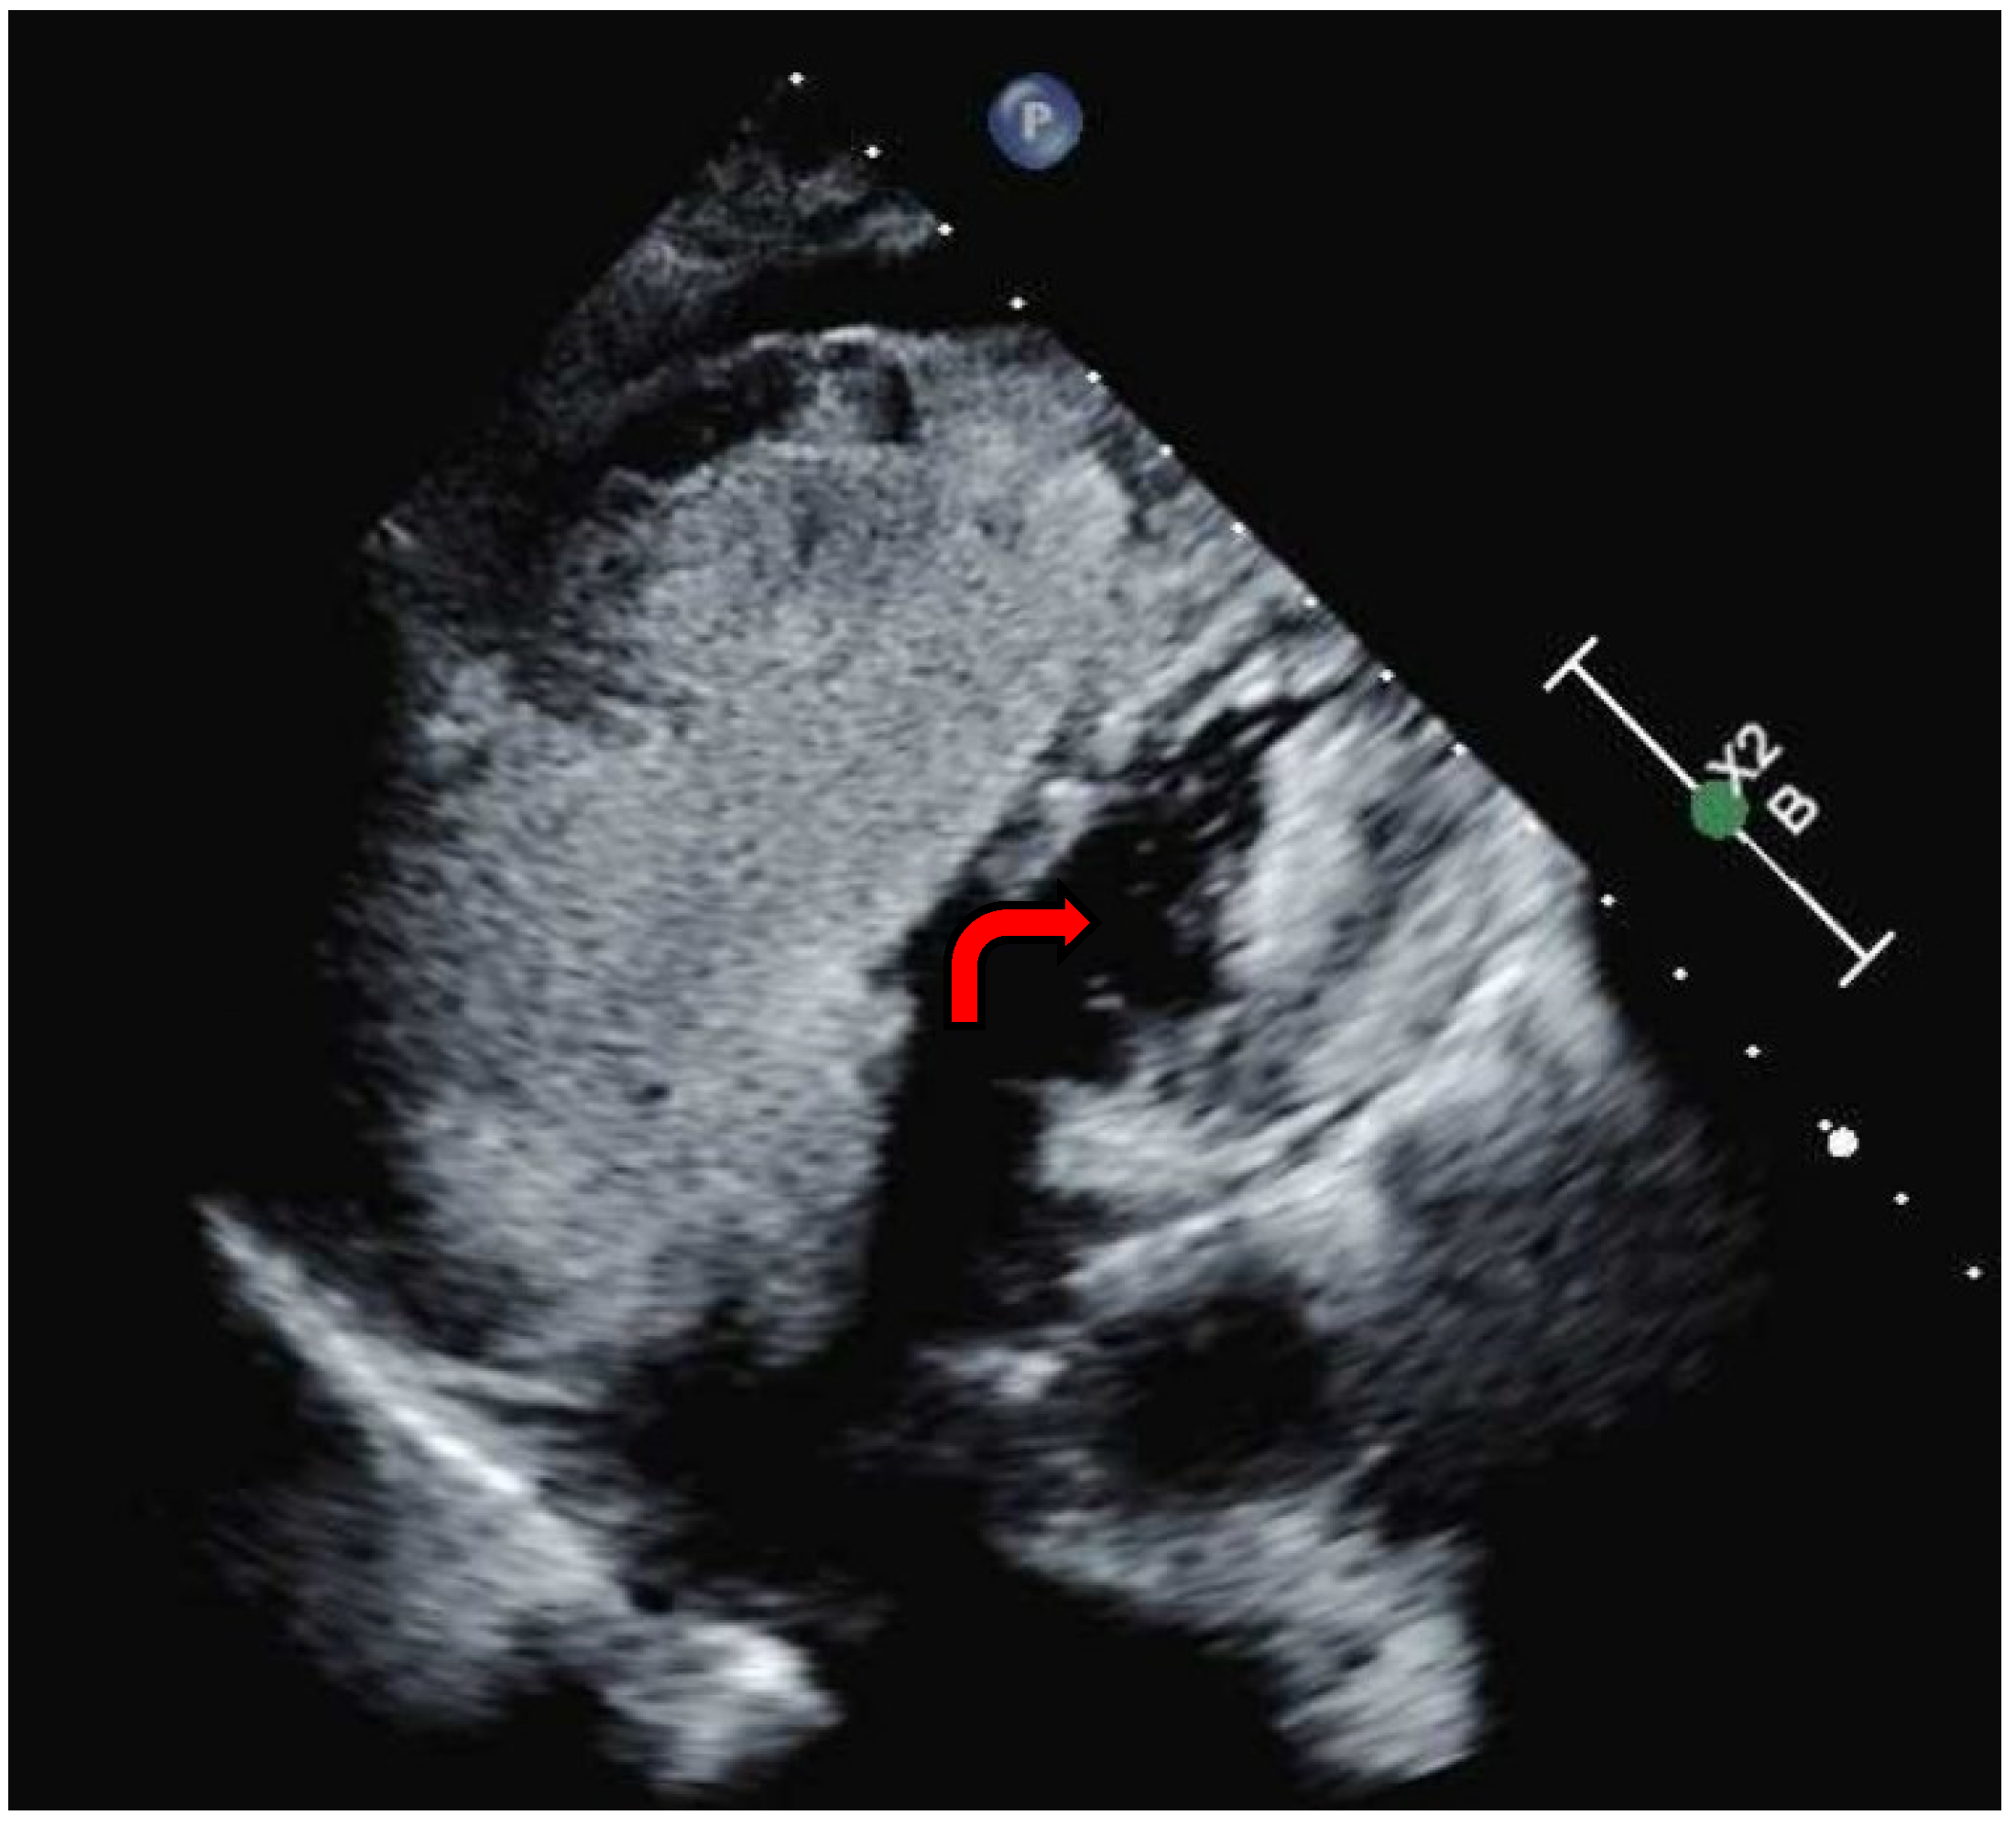

In light of these findings and with a suspicion of a mixed presentation of Group I and Group II PH, the decision was made to promptly wean pulmonary vasodilators. The patient was maintained on inhaled nitric oxide and norepinephrine. However, repeated attempts to reduce vasopressor dosage and epoprostenol resulted in persistent hypotension and severe hypoxia. A multidisciplinary meeting was convened to establish the goals of care and evaluate the patient’s clinical trajectory and available therapeutic options. Review of the prior echocardiogram, performed with a bubble study, revealed an intracardiac shunt (Figure 5, Video S1), consistent with an atrial septal defect (ASD). It was postulated that the pulmonary edema and worsening hypoxia could have been secondary to the intracardiac shunt, in conjunction with left ventricular dysfunction resulting from prolonged right ventricular failure. Consequently, a decision was made to resume titration of the epoprostenol, supported by the use of vasopressin and dopamine to sustain the mean arterial pressure above the mPAP, thereby minimizing intracardiac shunting and improving right ventricular perfusion.

Figure 5. Transthoracic echocardiography with agitated saline study (bubble study). The red arrow illustrates agitated saline in the left ventricle.